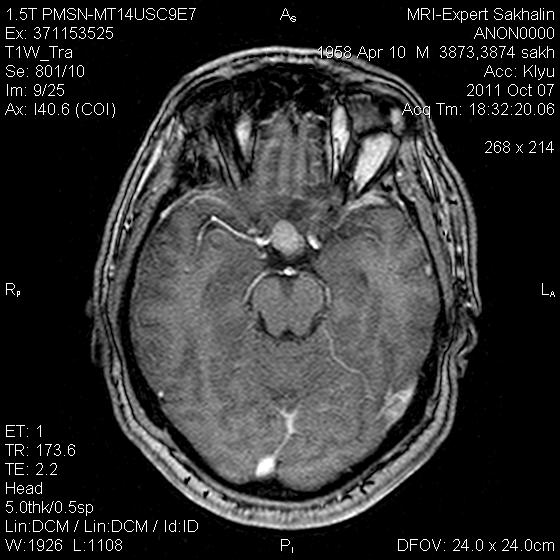

Аденома гипофиза

Вот такая аденома гипофиза сегодня.Мужчина с жалобами на снижение зрения.

постконтраст

Публикации: 175

Мне кажется что это все же не аденома, может глиома хиазмы ? (воронки гипофиза)? Или еще какое-нибудь объемное образование.... Что то меня смущает, еще не поняла что, но В любом случае наверное я бы однозначно не писала что это аденома, а выставила бы весь диф. ряд.

Танюша, обычно пишем "образование хиазмально-селлярной области"

Присоединяюсь к последнему коментарию, все таки откуда растет по моему мнению трудно однозначно сказать, лучше себя обезопасить написав "объемное образование хиазмально-селлярной области"